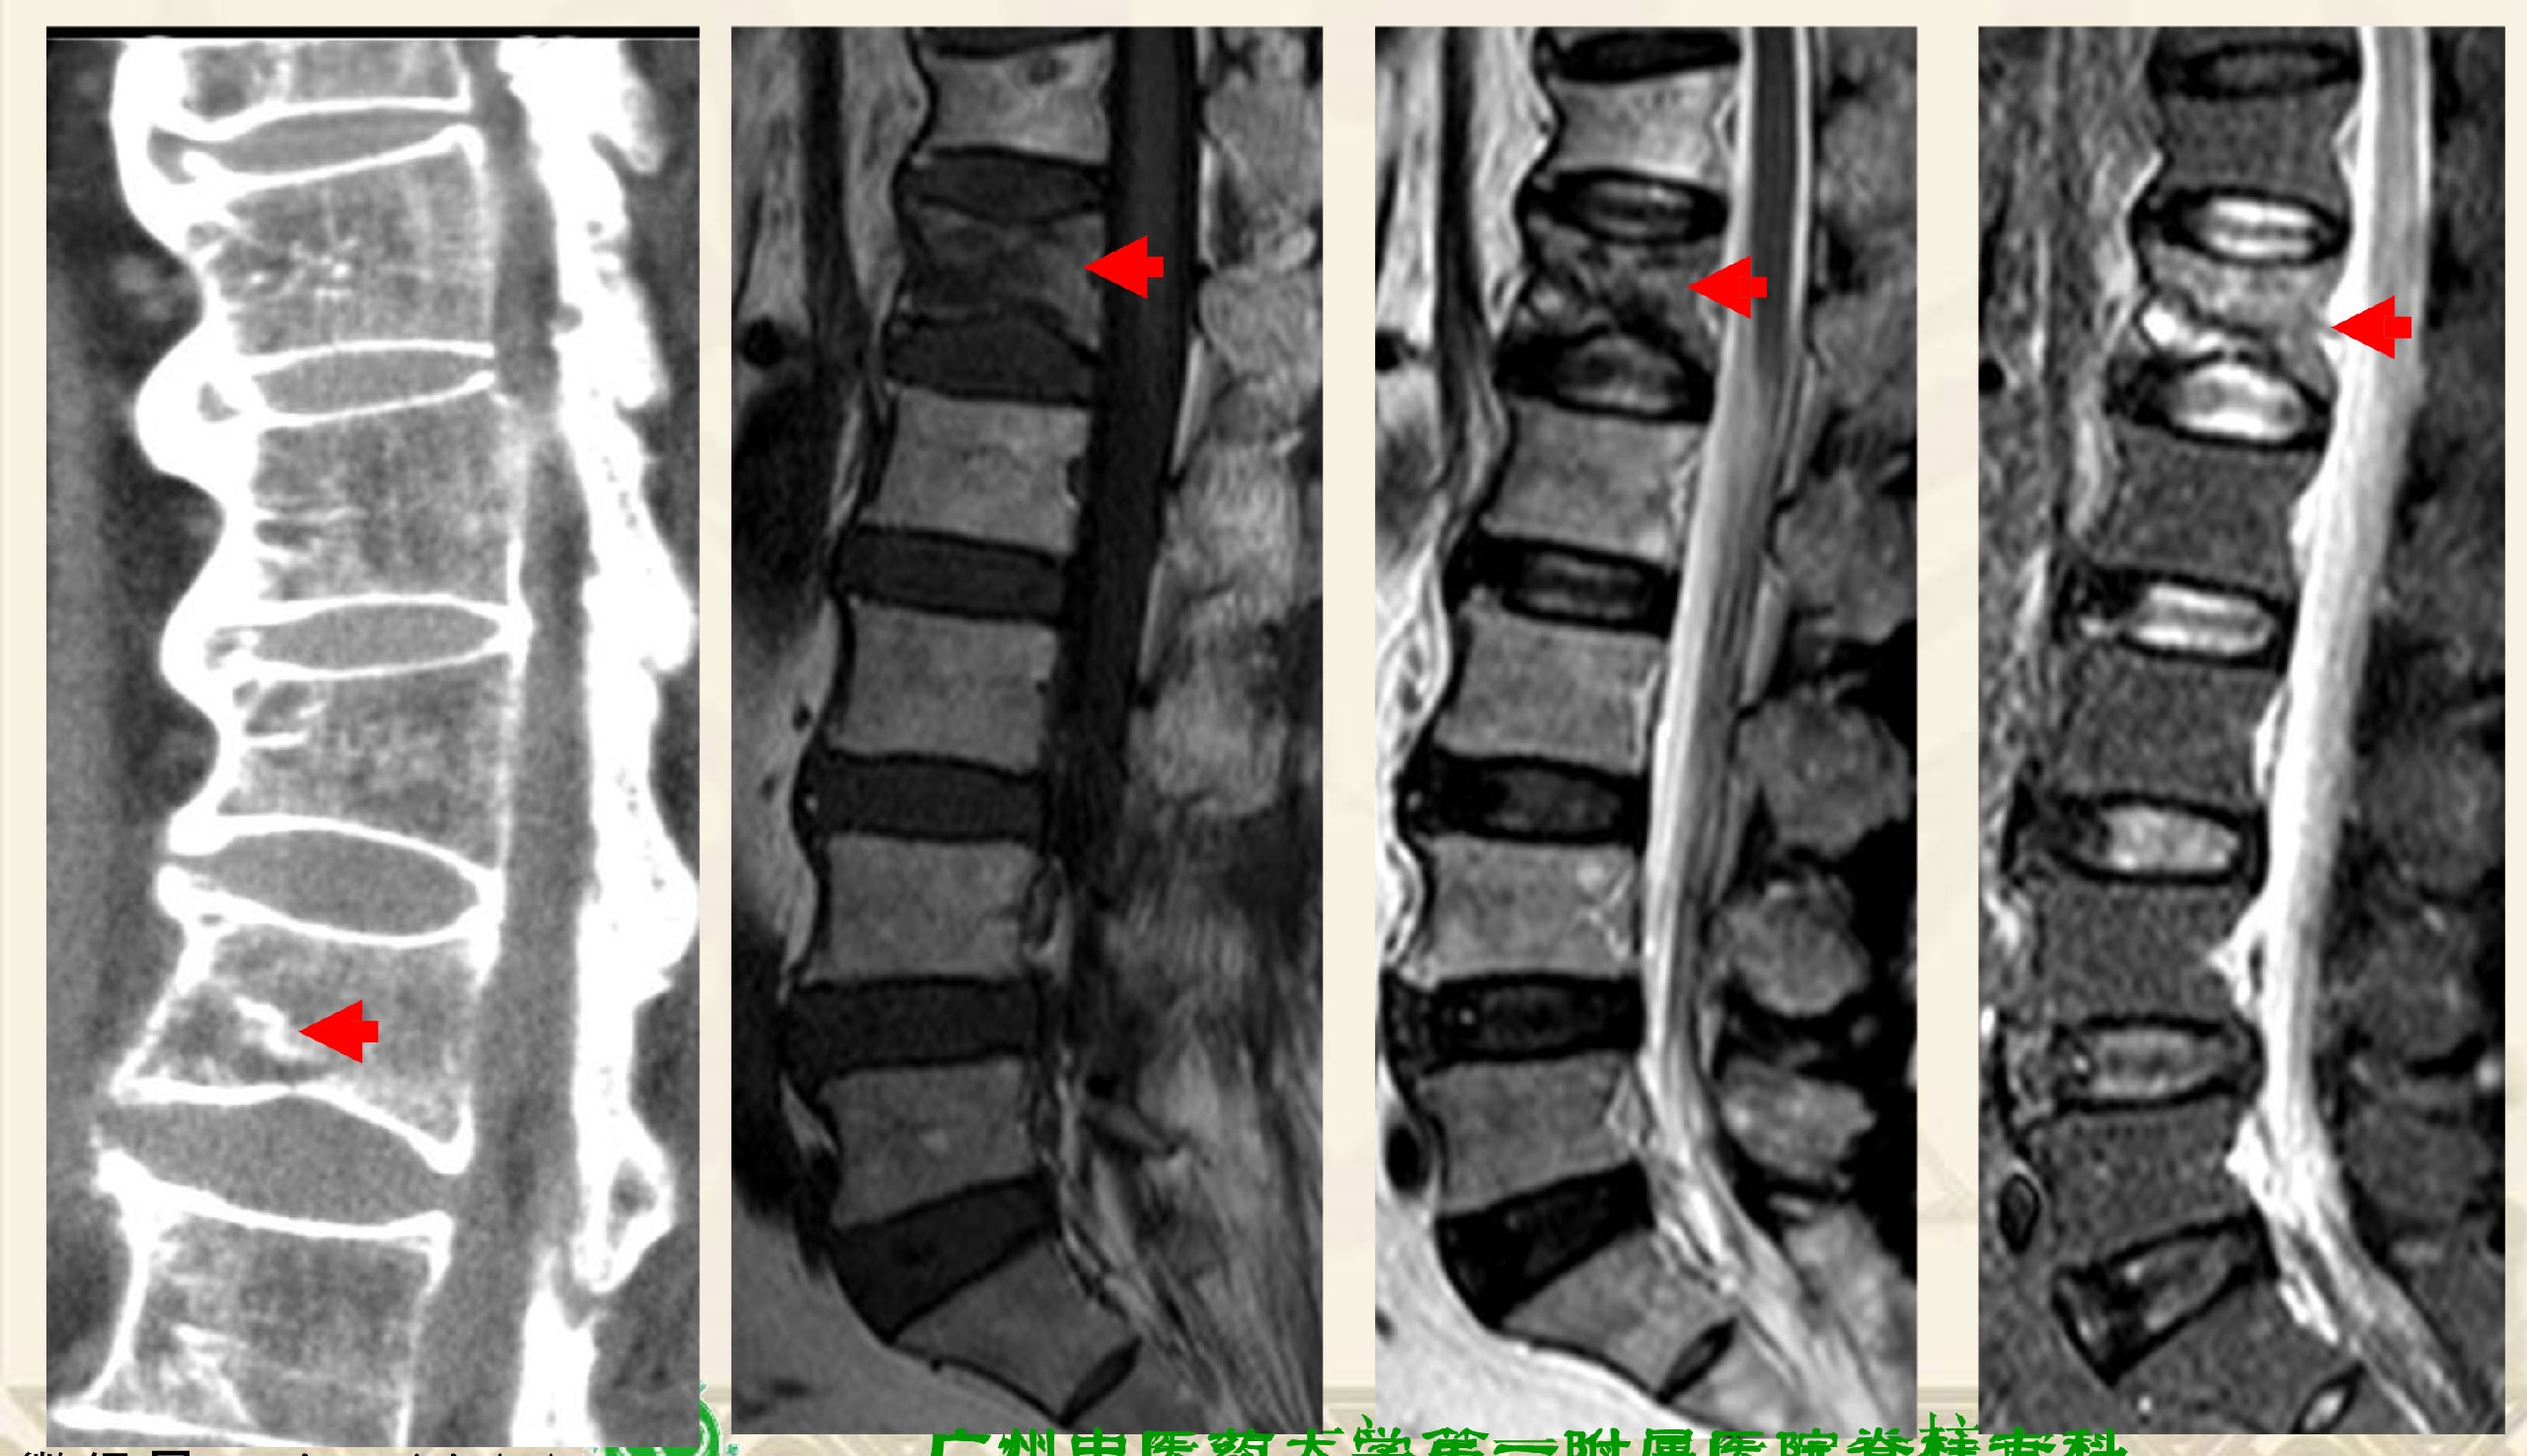

两大类型:①压缩后嵌插型,②压缩后自动复位裂隙型

压缩后嵌插型

压缩后自动复位裂隙型

压缩后嵌插型骨折线,CT:高密度带、MRI低信号带。

压缩后自动复位裂隙型,CT:裂隙,MRI:低信号区(气体)

CT:裂隙,MRI:高信号区(液体)